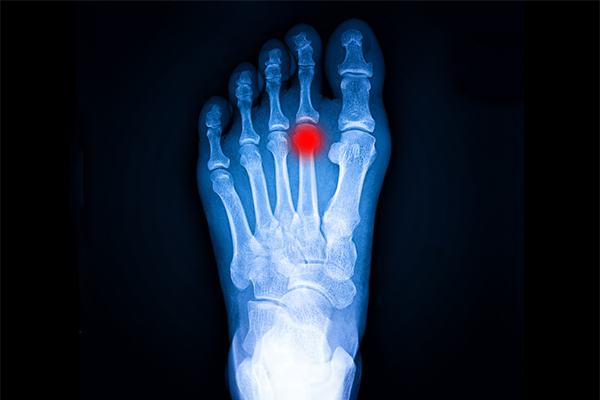

26 Mar 2024Las infiltraciones en el pie desempeñan una función relevante en la podología, permitiendo reducir el dolor de una forma rápida y eficaz. Son una técnica cada vez más utilizada para tratar diversas patologías del pie y del tobillo.

Las infiltraciones pueden realizarse con fines diagnósticos, antiinflamatorios y regenerativos dependiendo del medicamento y técnica utilizada.

Las infiltraciones mediante corticoides más habituales se realizan en procesos inflamatorios agudos, para disminuir la inflamación de los tejidos y mejorar la sintomatología del paciente (fascitis plantar, artritis, etc).

Para procesos inflamatorios crónicos o de larga duración donde hay una degeneración del tejido (como una fasciosis), se utilizan otras sustancias que tienen como objetivo principal regenerar el tejido lesionado.

Por esta razón, el PRP se utiliza en diversas condiciones, como: fascitis plantar (fasciopatías), tendinitis (tendinopatías), artrosis en los pies, osteocondritis, retraso en la curación de fracturas, lesiones de ligamentos, etc.

Otro factor importante para garantizar el éxito del tratamiento consiste en el uso de aparatología médica como el ecógrafo o fluoroscopio (intensificador de imagen de Rx) durante la infiltración, esto permite depositar el medicamento estratégicamente en la zona dañada.